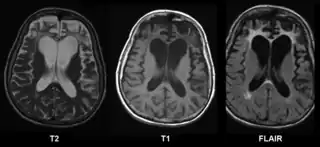

![]() Resonancia magnética cerebral en un caso de Enfermedad de Pick | ||